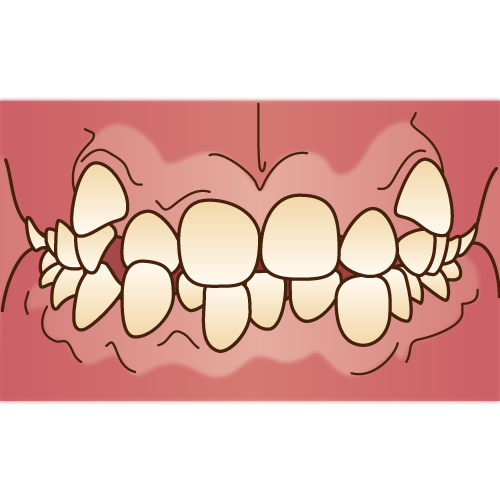

歯並びが悪いと、磨き残しが残りやすくなり、虫歯や歯周病になりやすくなり、噛み合わせが悪いと、歯や顎関節に負担がかかります。

凸凹の歯並びや、出っ歯や受け口がコンプレックスであるのなら、矯正で綺麗な歯並びになると、自己肯定感も上がるので、とても有効な治療だと思います。

矯正治療を受けたい最初の動機は、見た目の改善だとしても、矯正治療を受けることで、歯並びや噛み合わせが良くなり、結果的に上述したような、虫歯や歯周病のリスクの軽減、歯や顎関節の負担も軽減も出来ます。